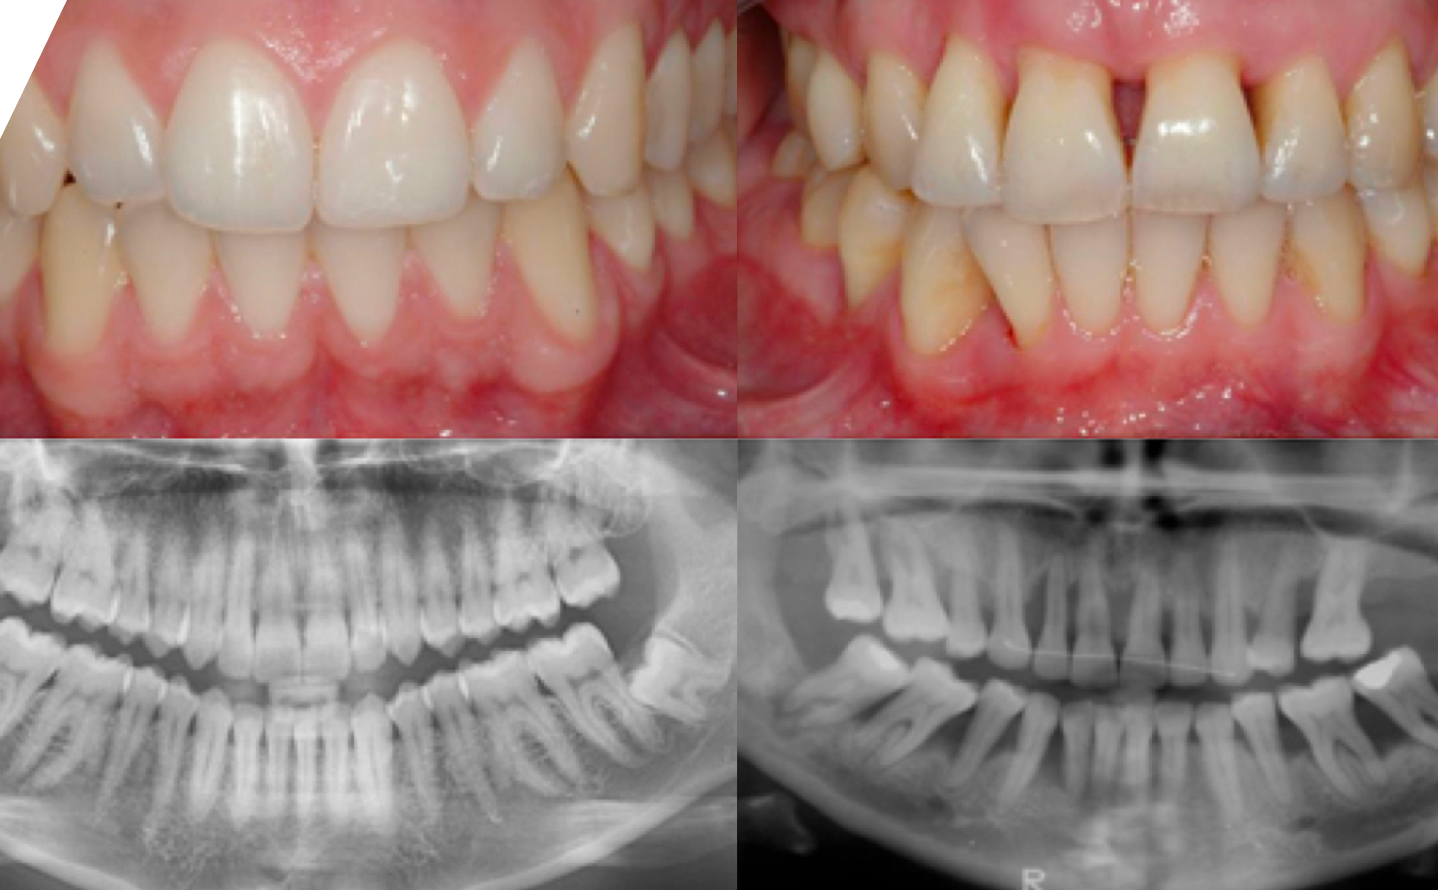

Parodontitis ist eine schwere Zahnfleischentzündung, die das Weichgewebe schädigt und den Knochen zerstört, der Ihre Zähne stützt. Parodontitis kann dazu führen, dass sich die Zähne lockern und kann zum Zahnverlust führen. Parodontitis ist häufig, aber weitgehend vermeidbar. Dies ist in der Regel das Ergebnis von unzureichender Mundhygiene ohne Zahnzwischenraumbürstchen und Zahnseide. Mindestens zweimal täglich bürsten, täglich Zahnzwischenraumbürstchen und Zahnseide verwenden und regelmäßige zahnärztliche Untersuchungen durchführen, kann Ihre Chancen auf eine erfolgreiche Behandlung von Parodontitis bzw. Zahnfleischentzündung erheblich verbessern und auch die Entstehung von entzündetem Zahnfleisch verringern.

Zahnfleischtaschen sind die ideale Umgebung für das Bakterienwachstum (37 ° C, feucht und anaerob (kein Sauerstoff)). Sie können unmöglich zu Hause gereinigt werden. Je tiefer die Tasche (z.B. 6 mm), desto höher ist die Bakterienbelastung. Mit jeder Mahlzeit, die Sie zu sich nehmen, sammeln sich in diesen Taschen mehr Nahrungsmittel, die die Bakterien zusätzlich ernähren und so das weitere Wachstum unterstützen. Wenn die bakterielle Belastung zunimmt, nimmt der Knochen um Ihre Zähne ab und schließlich lockern sich Ihre Zähne. Unbehandelt ist die Entfernung des Zahnes sicher.

- Eine anhaltende Zahnfleischentzündung kann Knochenentzündung verursachen, wodurch sich Taschen zwischen Ihrem Zahnfleisch und Zähnen bilden können, die sich mit Plaque, Zahnstein und Bakterien füllen. Mit der Zeit werden diese Taschen tiefer und füllen sich mit mehr Bakterien. Wenn Sie nicht behandelt werden, führen diese tiefen Infektionen zu einem Verlust von Gewebe und Knochen, und letztendlich können Sie einen oder mehrere Zähne verlieren. Auch chronische Entzündungen können Ihr Immunsystem belasten.